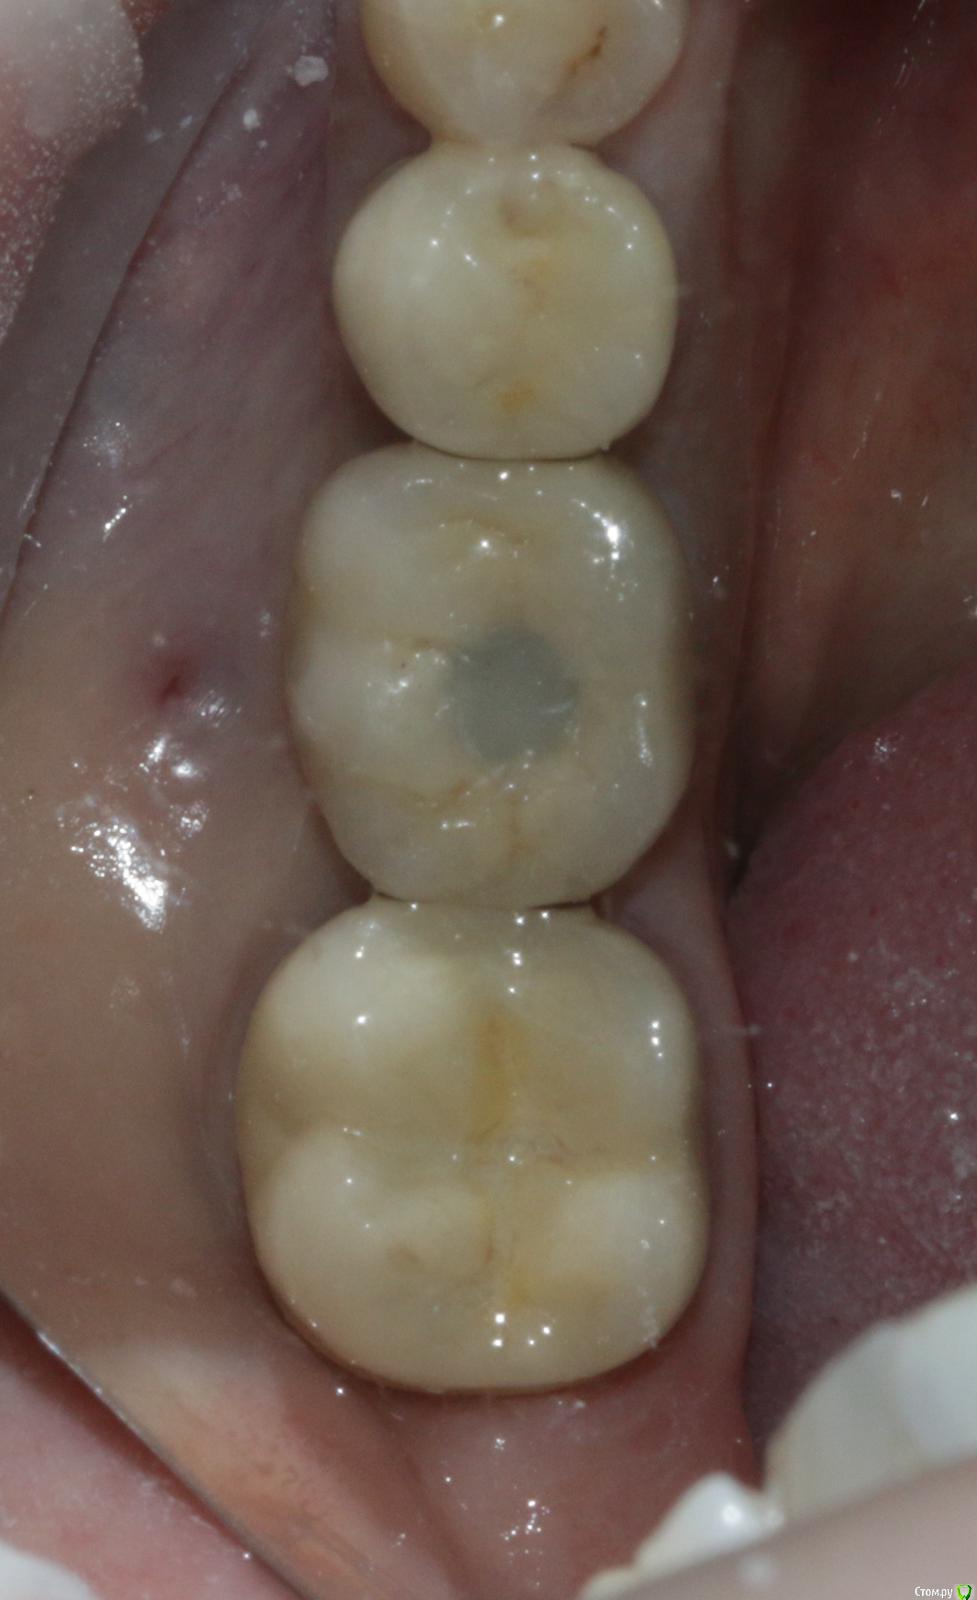

Ильдар Опубликовано 29 марта, 2015 Поделиться Опубликовано 29 марта, 2015 Коллеги, здравствуйте!Вот демонтировал старье. мк на зубы.имплант 4310, поставил поглубже.мк на имплант - техник прислал коронку с шахтой и абатмент,я склеил на fuji1. закрутил на 35 н.залепил не очень красиво , но с плавиковой, силаном и олбонд 3. думаю надежно.контрольный прицельный есть, видимо забыл его. извиняюсь за нечеткие fото. буду рад отзывам 3 Ссылка на комментарий

k.t.m. Опубликовано 29 марта, 2015 Поделиться Опубликовано 29 марта, 2015 все нра и прилегание коронок на зубах и витальность, но вот дентиум больше 1мм не стал бы заглублять,при отсроченном протоколе.и для одиночек снимаю закрытым методом-меньше возни 1 Ссылка на комментарий

Nemiroff Опубликовано 12 апреля, 2015 Поделиться Опубликовано 12 апреля, 2015 (изменено) в каталоге дентиум написано, что абатменты фиксируются усилием 25-30 ньютон. при большем усилии, если вы будете пытаться открутиться с конусной системы, то имеете высокий риск сломать винт, сорвать шахту винта или просто не открутить ничего. показаний к заглублению в данном клиническом случае нет на мой взгляд.а показания к круговой гирлянде не соседних зубах заключались в их витальности и необходимости сделать тонкий переход края коронки в тонкий уступ? Изменено 12 апреля, 2015 пользователем Nemiroff Ссылка на комментарий

Dr.Sham Опубликовано 15 апреля, 2015 Поделиться Опубликовано 15 апреля, 2015 МК вообще должна быть либо по кругу с гирляндой, либо с плечом. Ссылка на комментарий